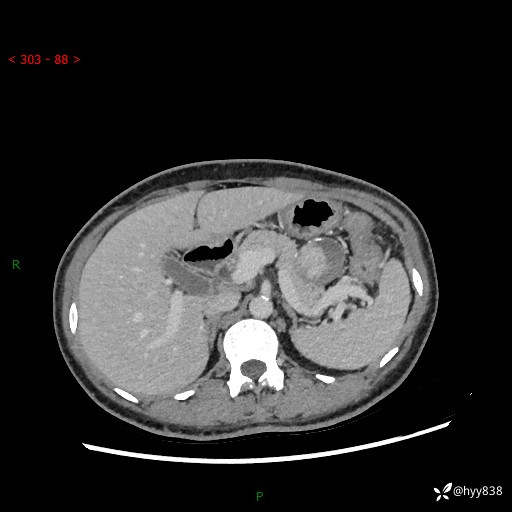

胰腺CT平扫

img